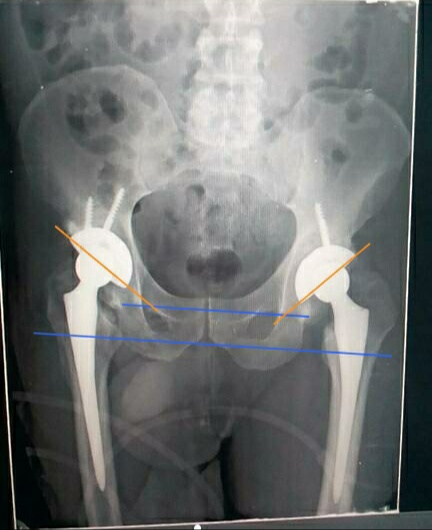

And what happens after a hip prosthesis?

Until a few years ago the implantation of a hip prosthesis was a surgery that was reserved for extreme cases in which the patient reached the operating room after having endured years of pain and a considerable loss of quality of life. Today, however, it is an increasingly common procedure as a result of the ageing of the population and the early detection of joint problems.